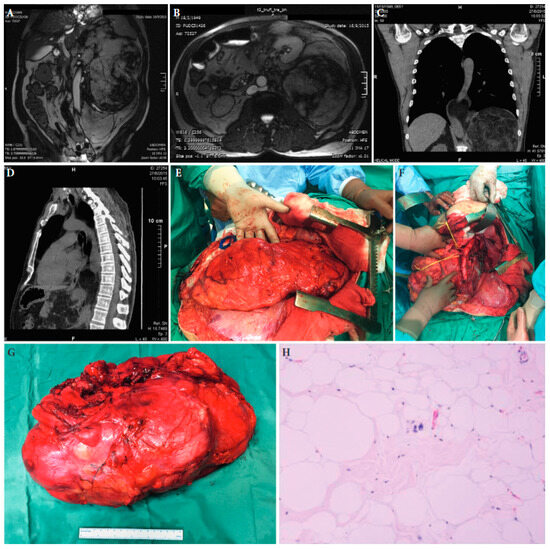

Frontline Extended Surgery

- Frontline extended surgery with compartmental resection and multivisceral surgery (i.e., liberal en bloc resection of adjacent organs and structures) increases local tumour control in low-grade sarcoma and liposarcoma and is associated with acceptable morbidity in expert centres.